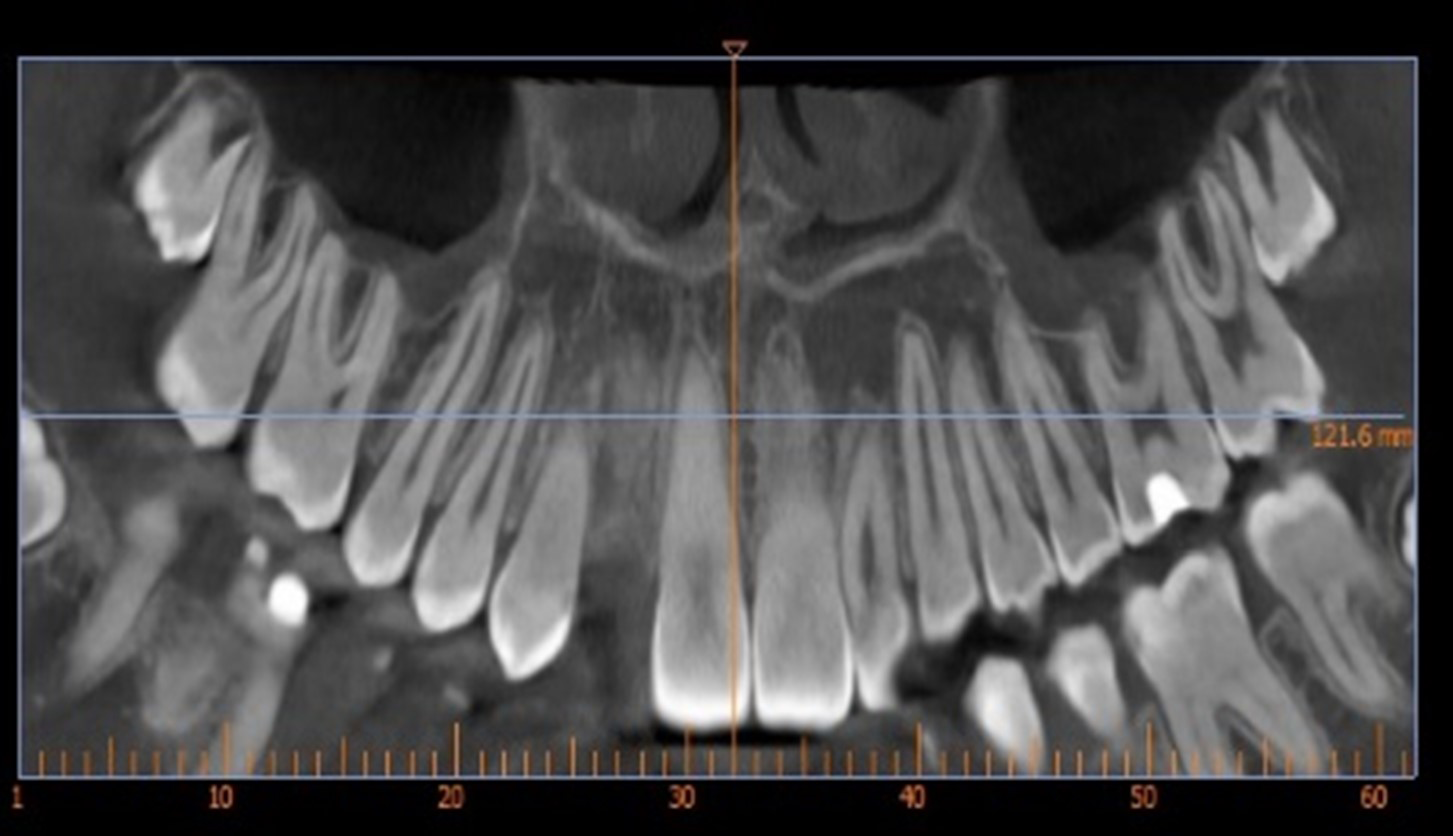

Skeletal Class II due to mandibular retrognathia, proclination of maxillary incisors, narrow arch creating a V-shaped arch, agenesis of 12, 31, 41, hyperdivergent facial pattern, moderate deep bite (2 mm), increased overjet (9 mm), asymmetric canine and molar Class II due to mandibular deviation to the left, maxillary midline deviation related to agenesis of 12, distal rotation of 35 and 45, and pronounced lower curve of Spee.

Two finishing stages were carried out after CBCT

18 aligners then 9 aligners (TruGen XR™)